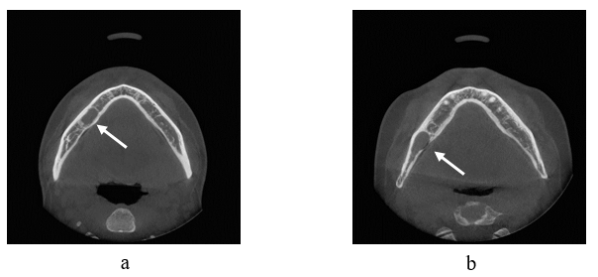

This section elaborates the method of the CAD system (Figure 2). The framework consists of two algorithms for detection of two types of lesions: Close border lesions (Type I) and Open border lesions (Type II) (Figure 1). This classification is not done on a medical basis but is used for research purpose only. In addition, the goal of this CAD scheme was not to detect a specific syndrome, rather any kind of abnormality regardless of the diseases type. Therefore, the classification of lesions considered here served as a generalized grouping of all type of abnormalities that could be found in dental CT images. A Close border lesion is defined as one that has a well-defined boundary around the lesion, and a Open border problem is one that has a broken boundary line around the lesion. Methods for detecting these two types of lesions are described in the later sections.

Figure 1: Illustration of two types of abnormality (a) Close border lesion, (b) Open border lesion